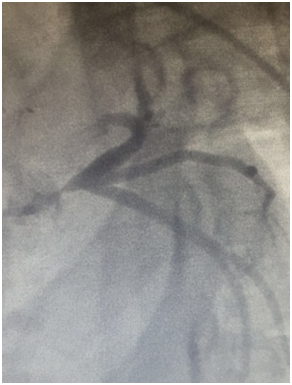

At day 20 after discharge, the patient experienced further episodes of chest pain she was readmitted for acute coronary syndrome coronary angiography showed that the bridge was no functional. Thus, percutaneous coronary angioplasty of the left main coronary artery was performed with implantation of a drug-eluting stent. No other events were reported, the follow up is about four months until now.